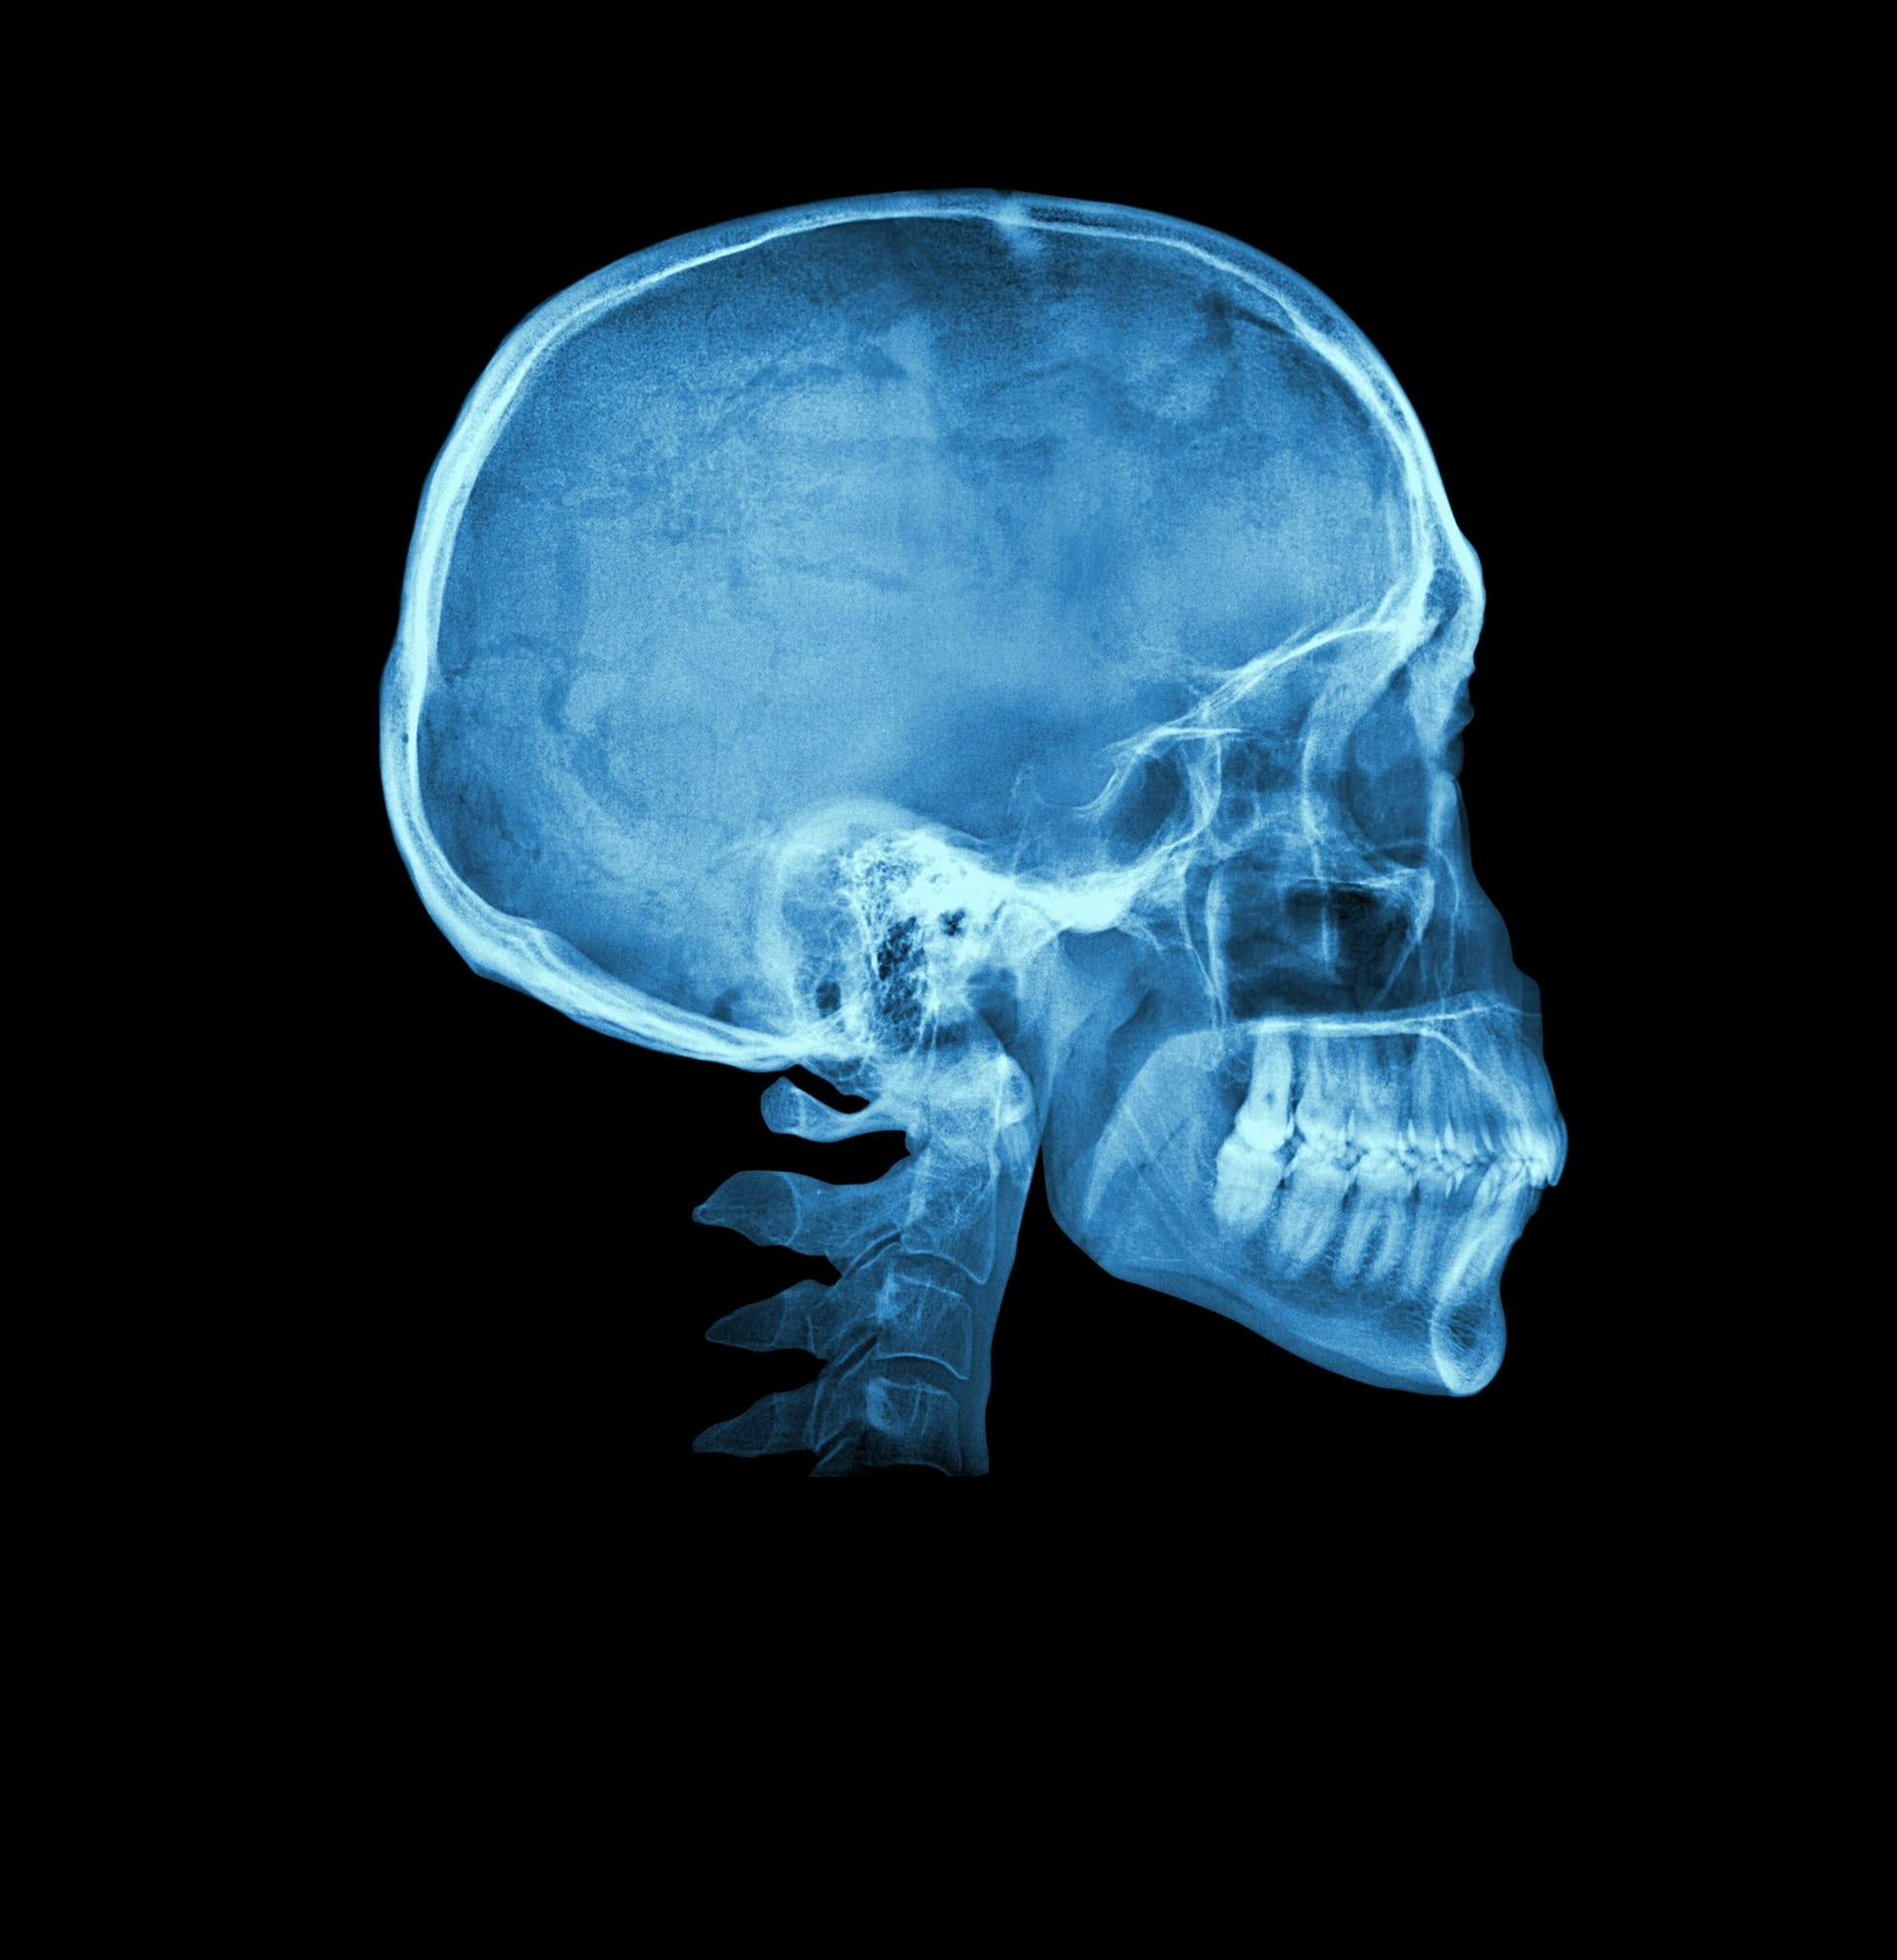

At Palm Beach Plastic Surgery Institute, we are committed to providing world-class craniofacial surgery in Palm Beach for children and adults for both congenital and acquired facial differences. Our team is led by renowned board-certified plastic surgeon, Dr Edward H Davidson MD FACS FAAP, with specialist fellowship training in craniofacial surgery and over a decade of experience. All surgical care is provided at the region’s leading hospital by dedicated specialists.

At Palm Beach Plastic Surgery Institute, we offer craniofacial surgery to address a wide range of conditions, including:

- Craniosynostosis: A condition involving the premature fusion of the skull bones, which can affect the shape of a child's head and potentially limit brain growth. Craniofacial surgery can correct this, allowing for normal brain development. Our team performs both open cranial vault remodeling and minimally invasive procedures aimed at reshaping the skull and relieving pressure on the brain caused by premature fusion of sutures in an infant’s skull.

- Complex craniofacial conditions: Our team is experienced in treating complex craniofacial syndromes such as Treacher Collins syndrome, Crouzon syndrome, Apert syndrome and other syndromic craniosynostoses. Our team is proficient in advanced frontofacial procedures for these conditions including monobloc and Lefort III advancements, facial bipartition, and box osteotomy.

- Jaw abnormalities: These can cause difficulties with speech, eating, and breathing. By reshaping and repositioning the upper and lower jaw through surgery, these issues can be addressed. Our team performs neonatal mandibular distraction osteogenesis for Pierre Robin Sequence, distraction osteogenesis for midface retrusion conditions and hemifacial microsomia, as well as orthognathic surgery for dental misalignment (malocclusion), sleep apnea and aesthetic facial skeletal contouring.

- Orbital (eye socket) reconstruction: We specialize in orbital reconstruction surgery, designed to restore the shape and function of the eye socket following injury, disease, or congenital differences.

- Cranioplasty: We are experts in reconstruction of skull defects that may occur trauma, cancer or brain-decompressive surgery. Our team uses state of the art regenerative techniques as well as autologous (patient’s own tissue) and alloplastic (artificial) implants depending on the scenario.